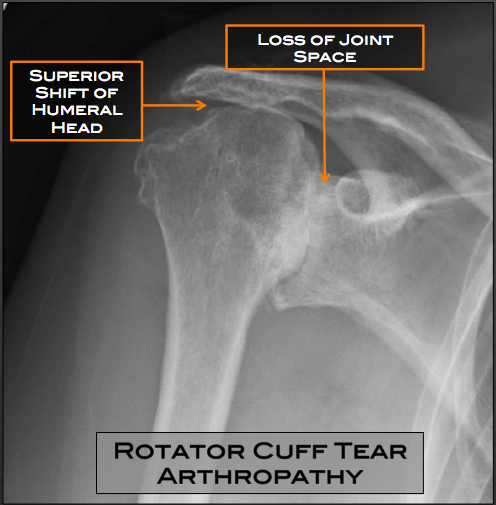

Shoulder Arthritis / Rotator Cuff Tears: causes of shoulder pain: B2 …

Shoulder Arthritis / Rotator Cuff Tears: causes of shoulder pain: How …

Shoulder Arthritis / Rotator Cuff Tears: causes of shoulder pain …

shoulder xray oa3 – DOCJOINTS//DR SUJIT JOS//Total joint replacements …

Shoulder Arthritis / Rotator Cuff Tears: causes of shoulder pain …

Shoulder Arthritis / Rotator Cuff Tears: causes of shoulder pain …

Shoulder Arthritis / Rotator Cuff Tears: causes of shoulder pain …

Shoulder Osteoarthritis Presentation and Treatment | Bone and Spine

Shoulder Arthritis / Rotator Cuff Tears: causes of shoulder pain …